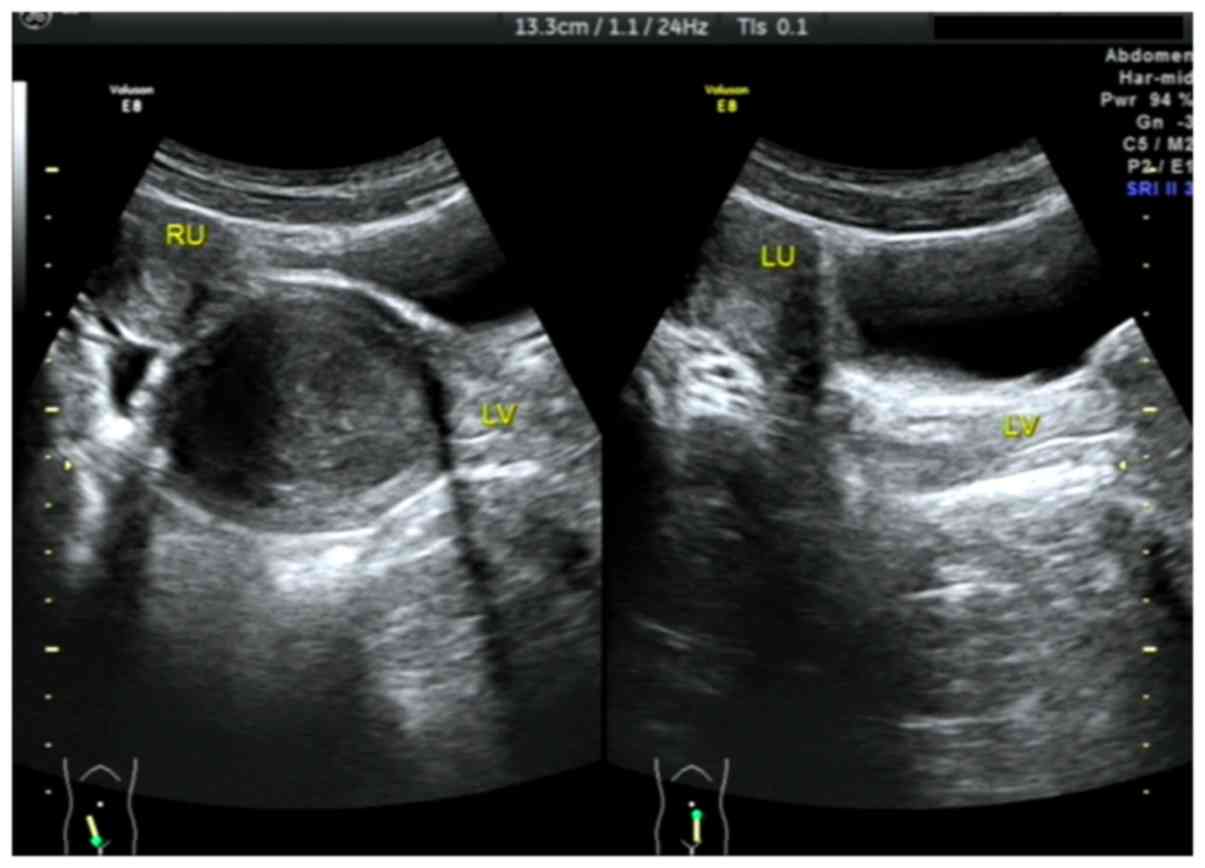

Out of the 15 patients with type I CVOS, there were 9 patients with right oblique septum and 6 patients with left oblique septum (Figs. 2–4). Among the 4 patients with type II CVOS, 3 patients had oblique septum on the right side and another on the left of the vagina (Fig. 5). In the 2 patients with type III CVOS, the septum was on the right side of the vagina (Fig. 6). Patients with types II (n=4) and III (n=2) CVOS exhibited an anechoic vaginal mass with an irregular shape and thickening wall, which was consistent with pathological findings.

Figure 2.

Type I congenital vaginal oblique septum syndrome. Sonograms were obtained from a 14-year-old female patient in sagittal pelvic planes demonstrating a normal right uterus and an oval cystic mass with dense floating echogenic dots behind the right septum vaginal cavity (left side of the figure), normal left uterus and left vagina (right side of the figure). RU, right uterus; LU, left uterus; LV, left vagina.